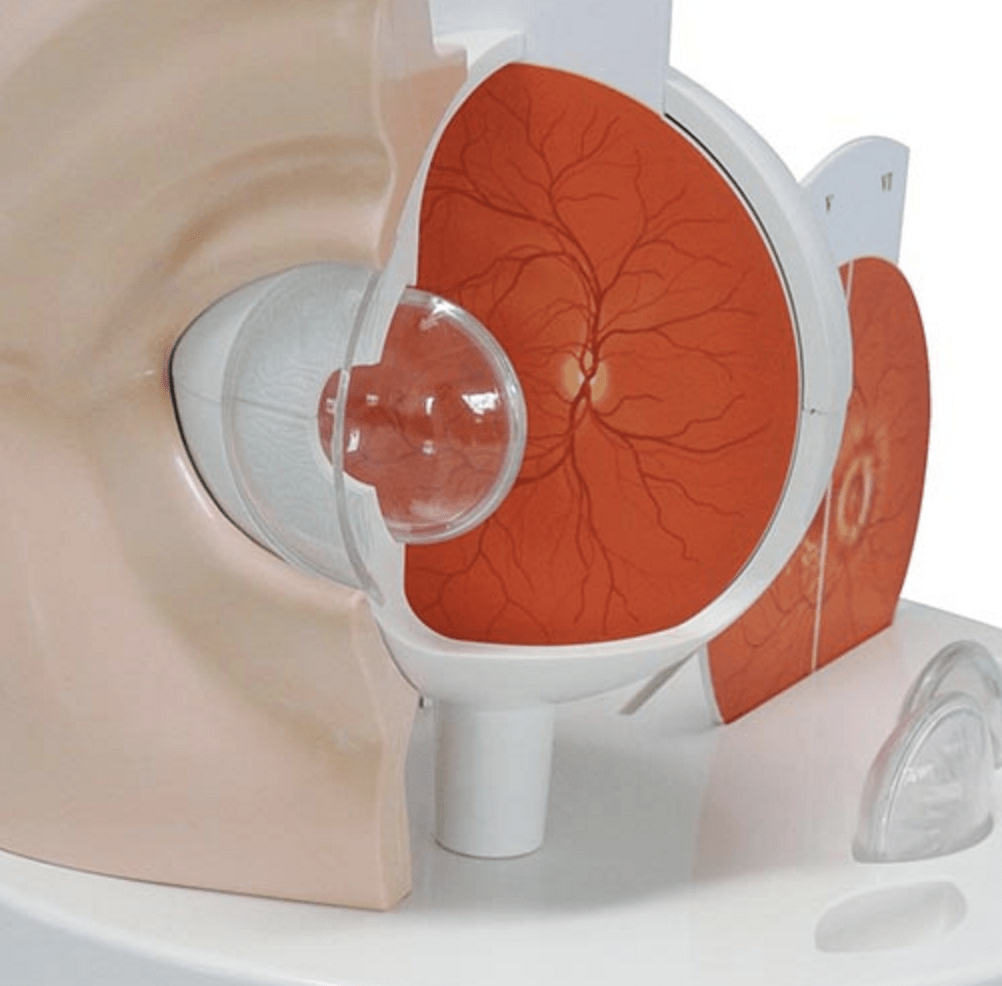

Salg af anatomiske modeller er det bærende element i eAnatomi, selvom vi også bruger mange ressourcer på at udvikle vores egne anatomiske materialer som fx plakater. Anatomiske modeller anvendes til forskellige formål og kan både vise afgrænset væv, organer samt organsystemer. Søger du en simpel model af knoglevæv eller måske en avanceret torso-model baseret på MRI teknologi, kan du finde det hele på eanatomi.com.